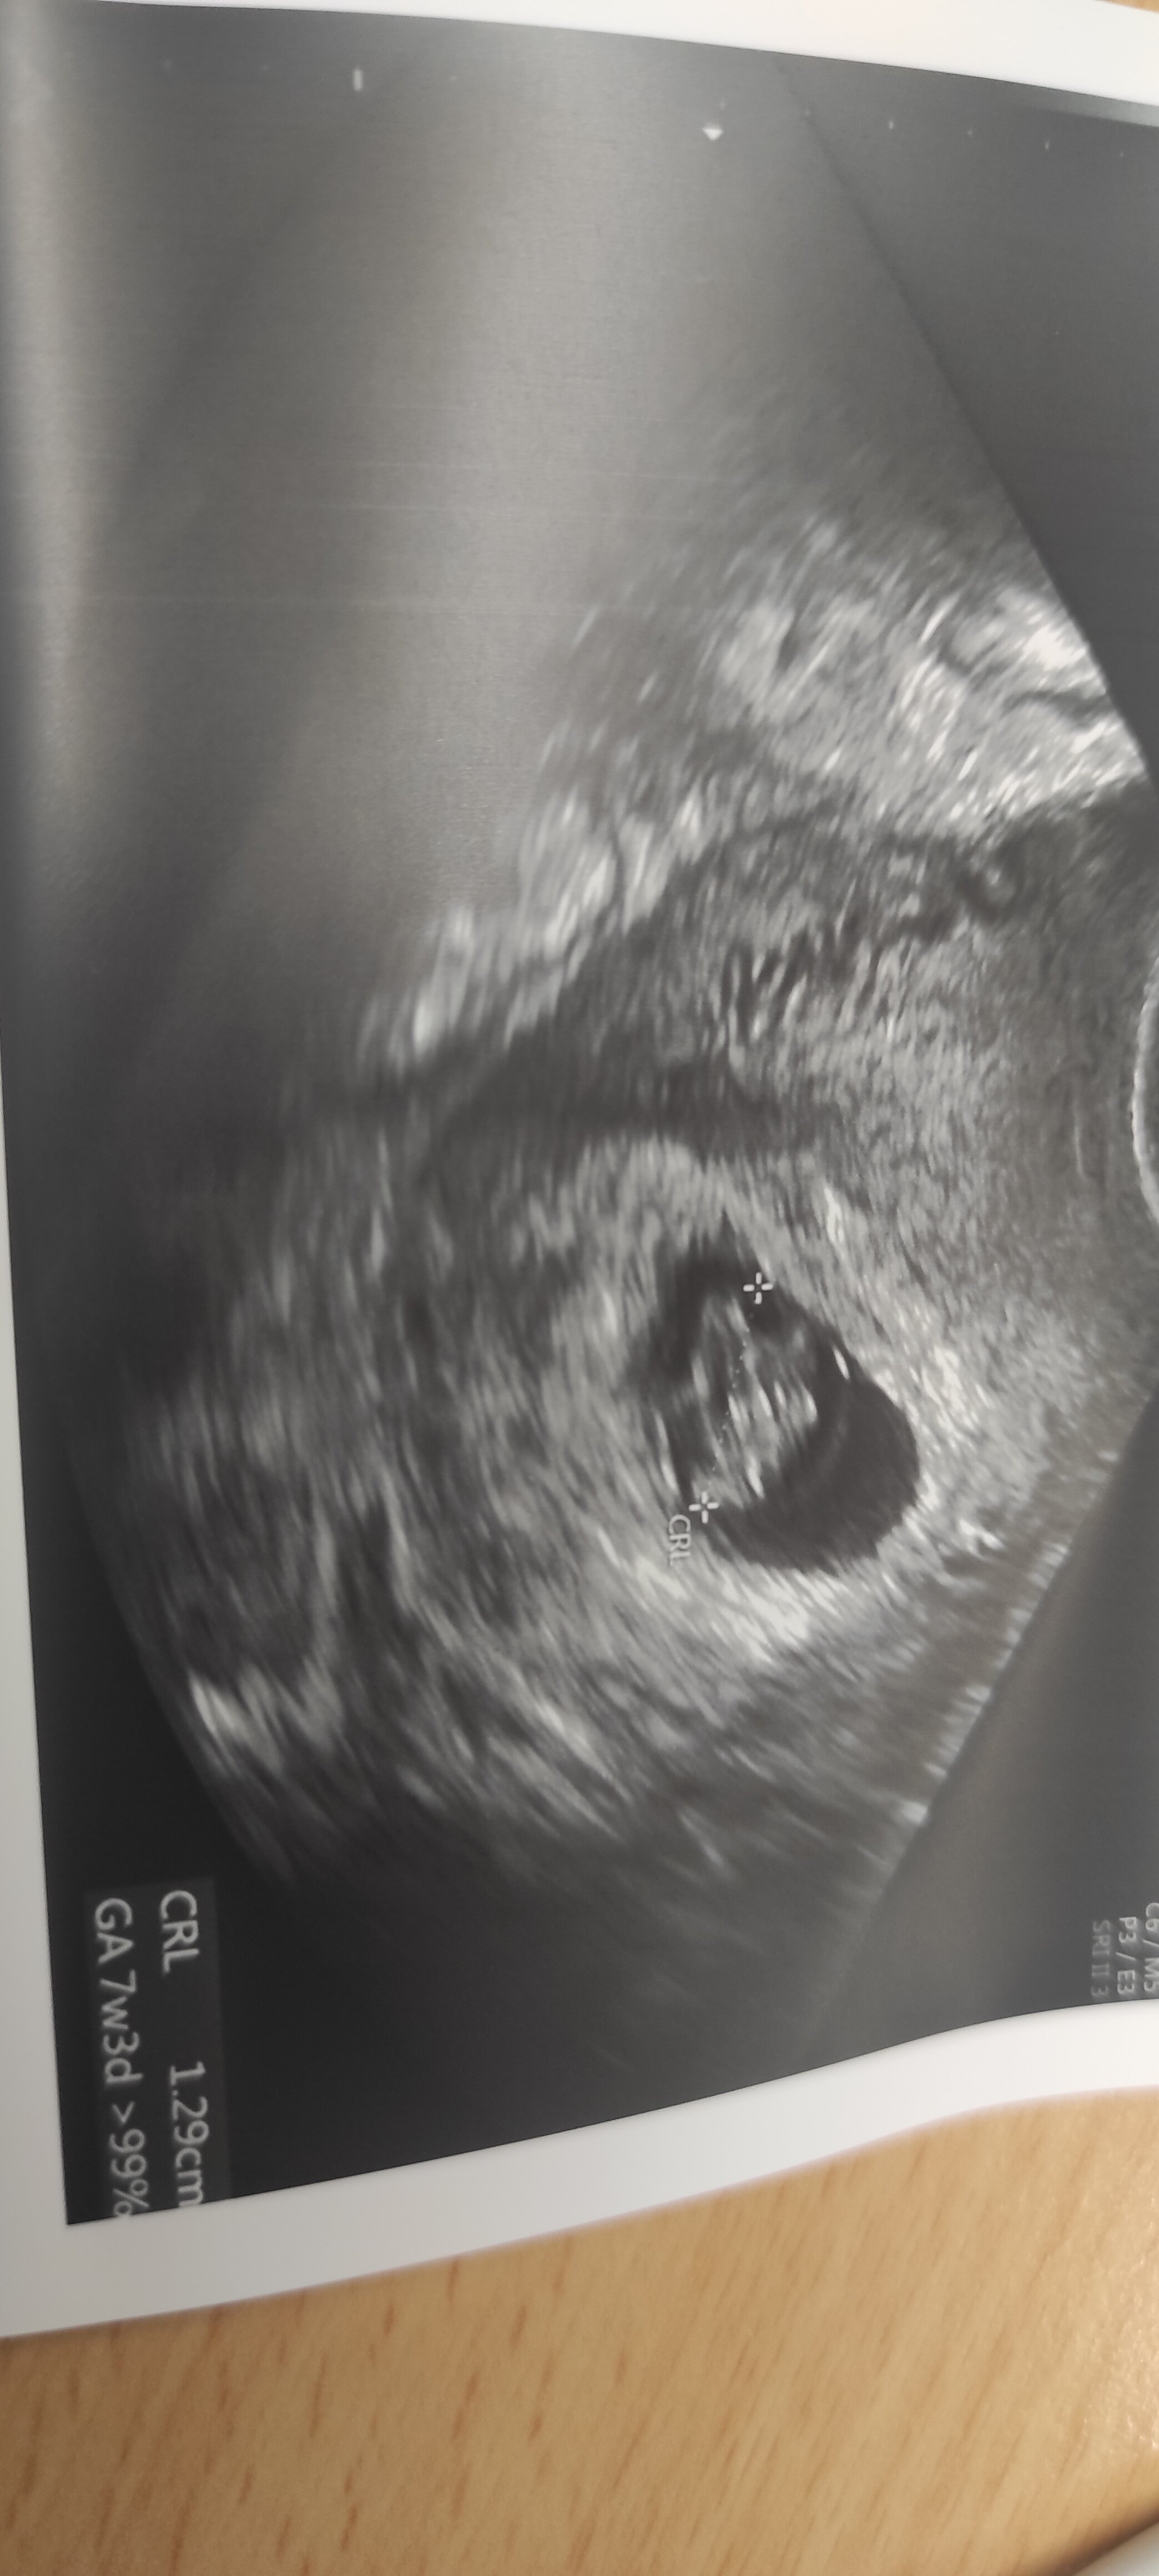

Hej 😁 ja już po wizycie ☺️ serduszko bije, póki co ciąża "żywa i zdrowa" 😁 dostałam całą listę badań do wykonania, USG piersi i parę innych rzeczy ☺️ idę też od razu na krzywą, w związku z insulinoopornością i cukrzycą w zeszłej ciąży.

Załączniki

• IMG_20220822_095244.jpg

IMG_20220822_095244.jpg

648,2 KB · Wyświetleń: 77